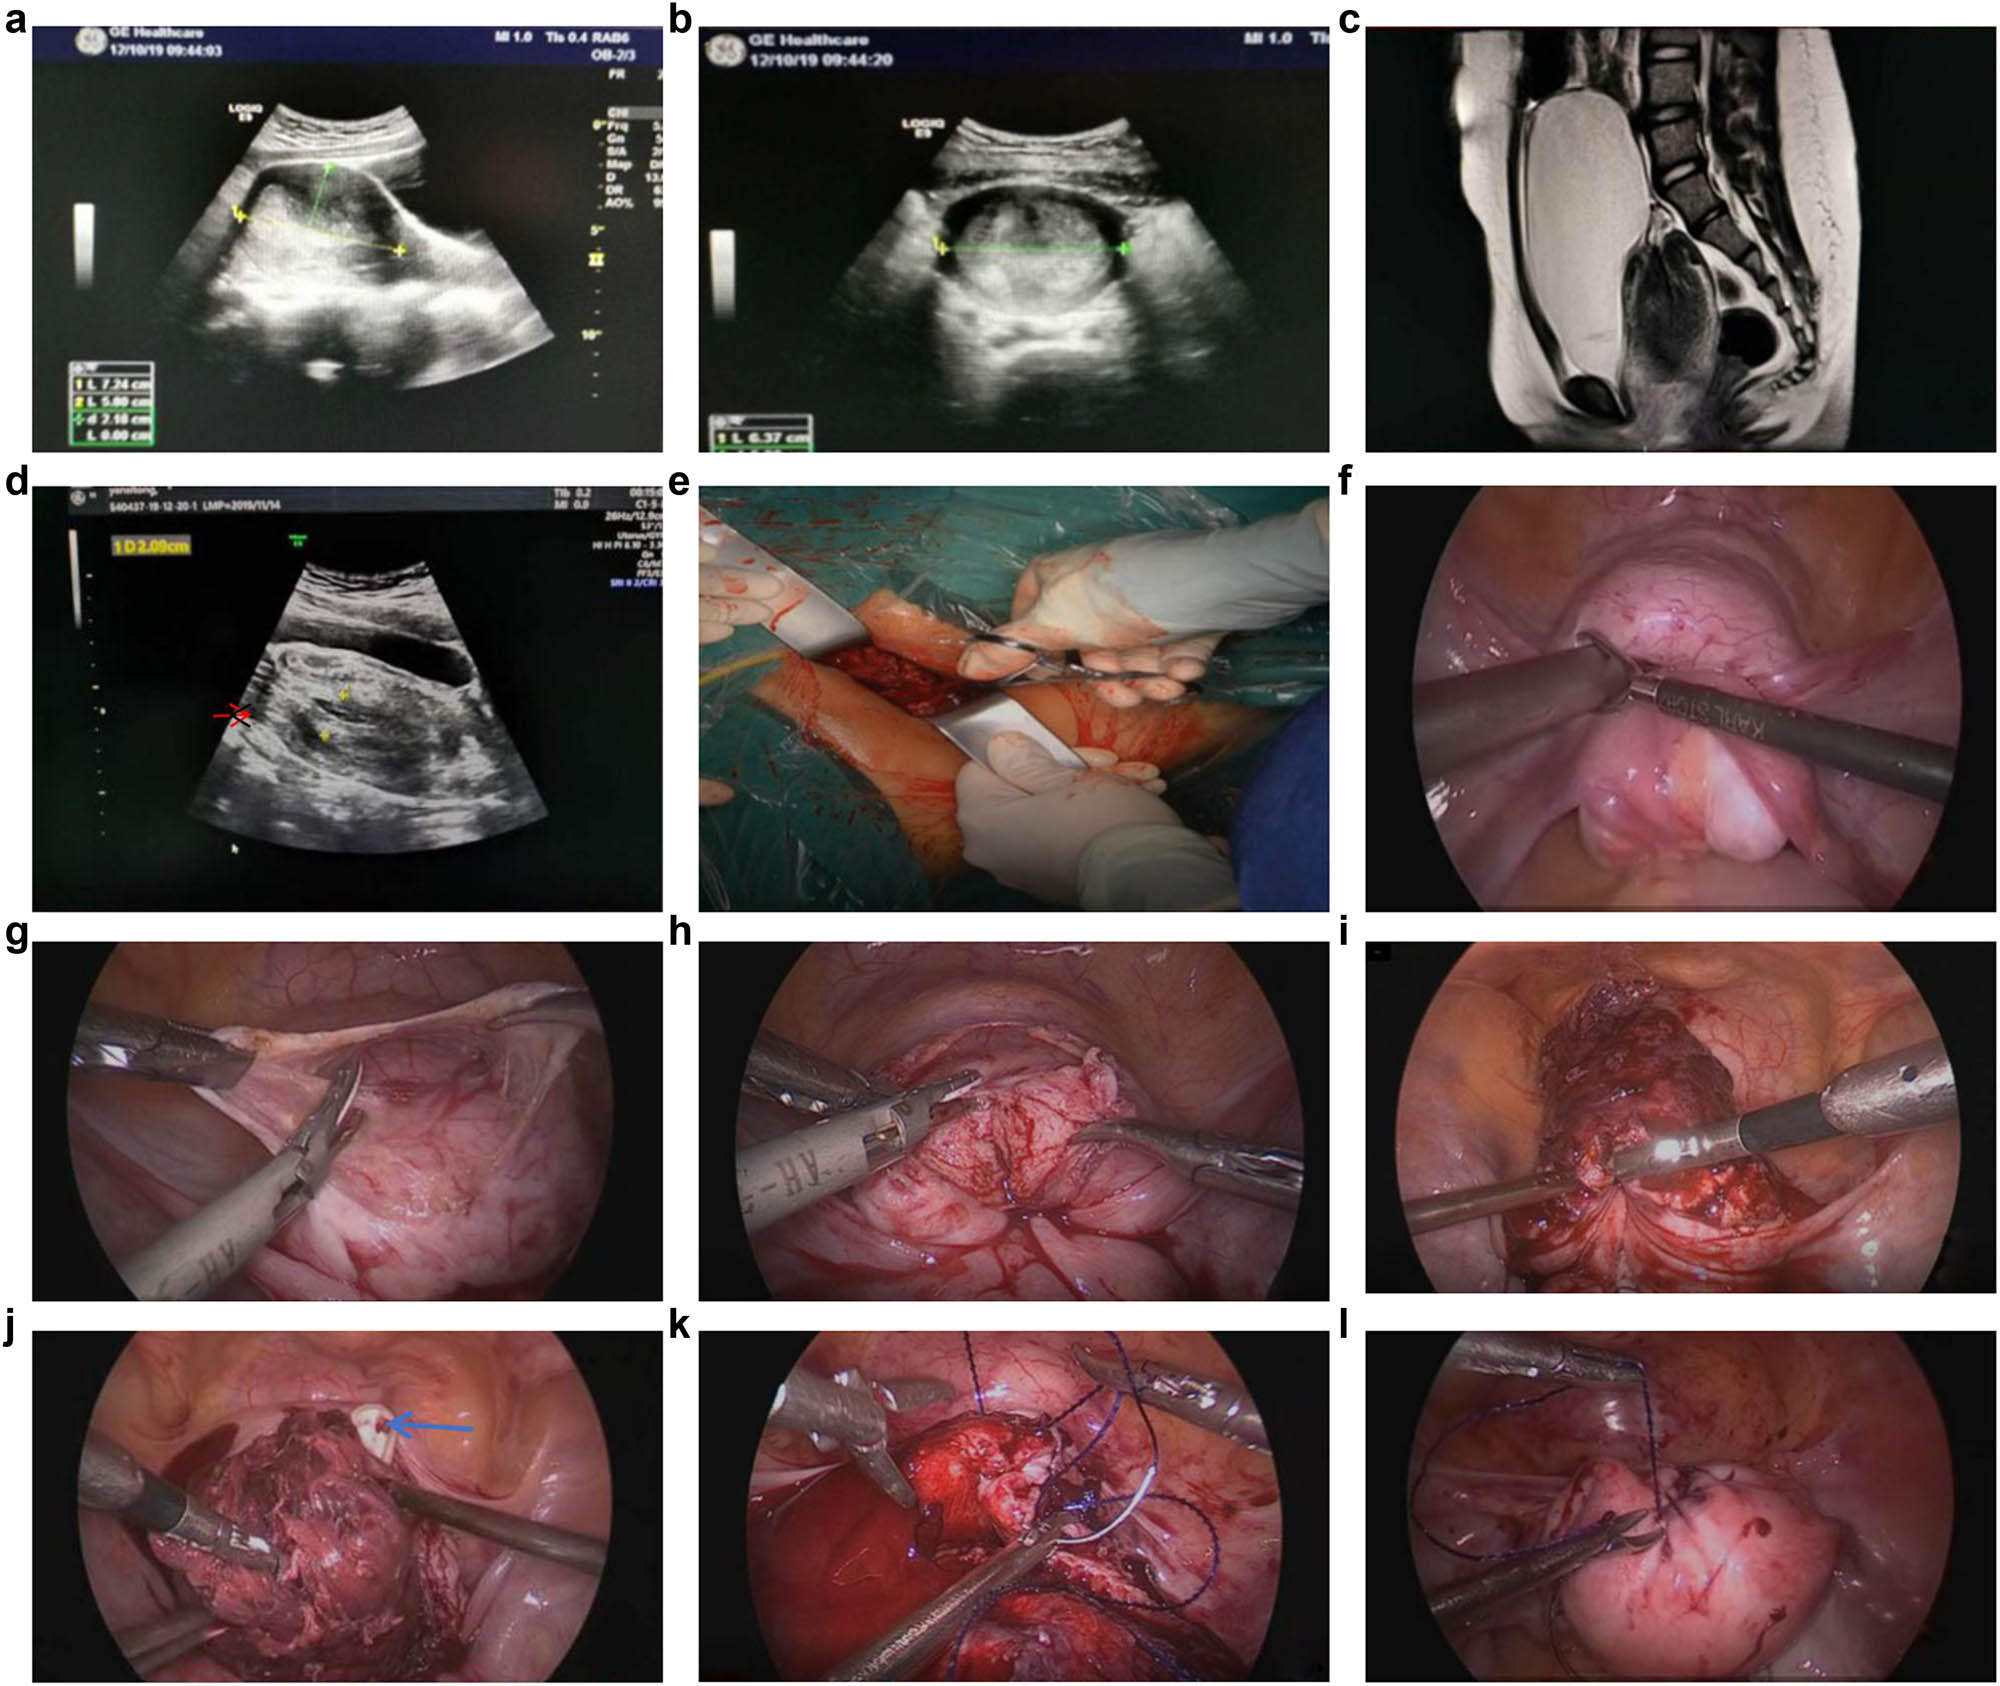

The patient was a 11-year-old Han Chinese girl without infectious disease history or special hereditary disease history in the family. She received GNRH treatment from Jiangxi Provincial Children’s Hospital 1 year ago after being diagnosed with precocious puberty. It was reported that the color ultrasound examination at that time revealed no abnormalities (no report was seen). On November 4, 2019, the patient presented to the outpatient department of our hospital because of repeated menstrual disorders. The color ultrasound results on the same day showed that the uterine size was about 64 mm × 56 mm × 49 mm, and the endometrial thickness was about 23 mm. The patient was prescribed with 1 Dydrogesterone tablet, twice per day for 20 days. Vaginal bleeding decreased slightly but did not stop. On November 24, the patient came to our hospital for further consultation, and the routine blood tests showed that Hgb was 95 g/L, the color ultrasound showed that the endometrial thickness was about 35 mm, and the remaining items were approximately the same as the previous one. This time, the patient was prescribed with 1 tablet of drospirenone and ethinylestradiol tablet (II), once every 12 h. Bleeding was significantly reduced but did not stop, and the routine blood test showed that HG was 103 g/L. On December 10, the patient came to our hospital for another re-diagnosis. The color ultrasound showed (Figure 1a and b) that the uterine size was about 72 mm × 65 mm × 58 mm, with even echoes from the muscular layer, and the endometrial thickness was about 42 mm, with uneven echoes, and a dark sieve-pore liquid was visible inside, which suggested that uterus was getting bigger and the endometrium was thickening. The patient felt occasional distending pain in the lower abdomen.

(a and b) Color ultrasound images (sagittal and transverse position) 10 days before the surgery. (c) MRI image after admission. (d) Color ultrasound image after admission (the arrow points to the ovary). (e) Intraoperative vaginal view. (f) Intraoperative laparoscopic view. (g) The uterine serosa was incised. (h) The anterior myometrium and the vagina were incised. (i and j) Uterus after incision (the blue arrow indicates the finger of the vaginal operator). (k) Suturing the vagina and the myometrium. (l) Uterus at the end of suturing.

On December 18, she experienced a sudden increase in vaginal bleeding, accompanied by severe pain in the lower abdomen, nausea, and vomiting, and a fleshy tissue about 6 cm in size could be seen at the vaginal orifice. On the same day, the patient came to our hospital after her family attempted to remove the fleshy tissue at home. The physical examination after admission showed a mass prolapsed from the vaginal orifice, about 6 cm in size, with a hard texture and uneven surface, and it was not possible to identify the cervical part with the vaginal palpation. The routine blood test at admission on December 18 showed that WBC was 24.57 × 109/L, N was 91.20%, and Hgb was 77 g/L; the admission diagnosis was: (1) vaginal neoplasm: submucous myomas delivery? uterine sarcoma delivery? (2) Moderate anemia. The patient exhibited symptoms of urinary retention after admission, which were spontaneously relieved afterward, abdominal pain was gradually relieved, and the protruded mass returned to the vagina. On the day of admission, a partial tissue of about 3 cm × 1 cm × 1 cm in size was removed with tissue forceps and sent for pathological examination. The results showed a smooth muscle tissue with intravascular hyperplasia, dilatation, and hyperemia visible inside, complicated with inflammatory cell infiltration, and a few endometrial glands and stroma on the surface. Then, Magnetic Resonance Imaging (MRI) was performed, and the results showed (Figure 1c): (1) complete uterine inversion, which oppressed the urethra and caused urinary retention of the bladder; and (2) vaginal effusion, given the patient had moderate anemia at admission and continued to bleed after admission. A 1.5 Iu isotype red blood cell suspension was administered to correct the anemia. Since the risk of infection was increased because the tissue once prolapsed out of the vaginal orifice and the hemogram had increased, piperacillin sodium, sulbactam sodium, and metronidazole were administered through intravenous drip for anti-infectious treatment.

A color ultrasound re-examination on December 20 showed (Figure 1d) that the uterus lost its normal form, the demarcation between the uterine body and the cervix was unclear, the size was about 88 mm × 60 mm × 55 mm, the uterine fundus was inverted to the cervical external orifice, chaotic hyper-level echoes with a range of about 66 mm × 21 mm could be detected inside, striped blood flows could be seen on Color Doppler Flow Imaging, and the echoes of the two ovaries were detected in front of the internal cervical orifice. These results suggested uterine inversion.

On December 20, laparoscopic exploration was performed to get a definite diagnosis and restore the normal anatomical position of the uterus. During the surgery (Figure 1e–l), it could be seen that the uterine fundus was completely depressed for approximately 6 cm, and bilateral attachments were cohesive in the depression of the uterine fundus. Our attempt to reposition the uterus failed, so we incised the serosal layer of the anterior uterine wall and pushed down the bladder, after which we incised the entire layer of the anterior wall muscle layer from the everted bottom to about 2 cm of the vaginal segment. The intrauterine tissues were in disorder, in a status of thickening, edema, and necrosis, without clear tumor-like tissues. We removed the messy intrauterine tissues from the uterine cavity (rapid intraoperative histopathology did not indicate malignancy), repositioned the uterus, restored its anatomical position, and sutured the anterior wall myometrium and the vaginal segment continuously according to the anatomical structure of the muscular and the serosal layers. The surgery went smoothly. During the entire operation, bleeding was about 50 mL, and the uterus was beautifully stitched, The pathological examination showed that the tissue had a polypoid structure, the glands were in the shape of small round tubes or fissures, stromal cells showed mild decidual degeneration, and the internal blood vessels were significantly increased, congestive, expanded, and bleeding, thus suggesting an asynchronous reaction between endometrial glands and stroma. Antibiotics continued to be administered postoperatively for anti-infection purposes, and the patient recovered moderately well and was discharged from the hospital after 3 days. Regular follow-ups were carried out via telephone or on an outpatient basis.